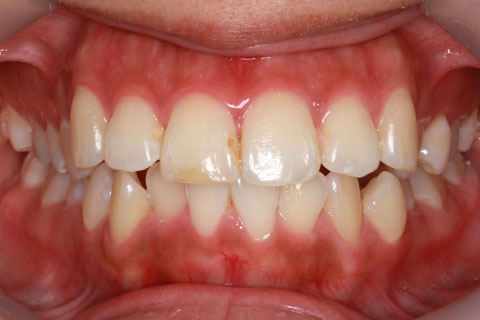

矯正期間18ヶ月

ハーフリンガル矯正2(上の歯のみ舌側矯正で治療)

治療前

治療中

治療後

- 年齢・性別

- 23歳女性

- 治療期間

- 1年6ヶ月

- 抜歯

- 上顎4番

- 治療費

- 110万円(税込み)

- 備考

- ハーフリンガル矯正

- 治療内容

- 上下前歯部凸凹の改善

- 施術の副作用(リスク)

- 裏側矯正の特性上、表側矯正と比較すると治療期間が長くかかる場合が多い。